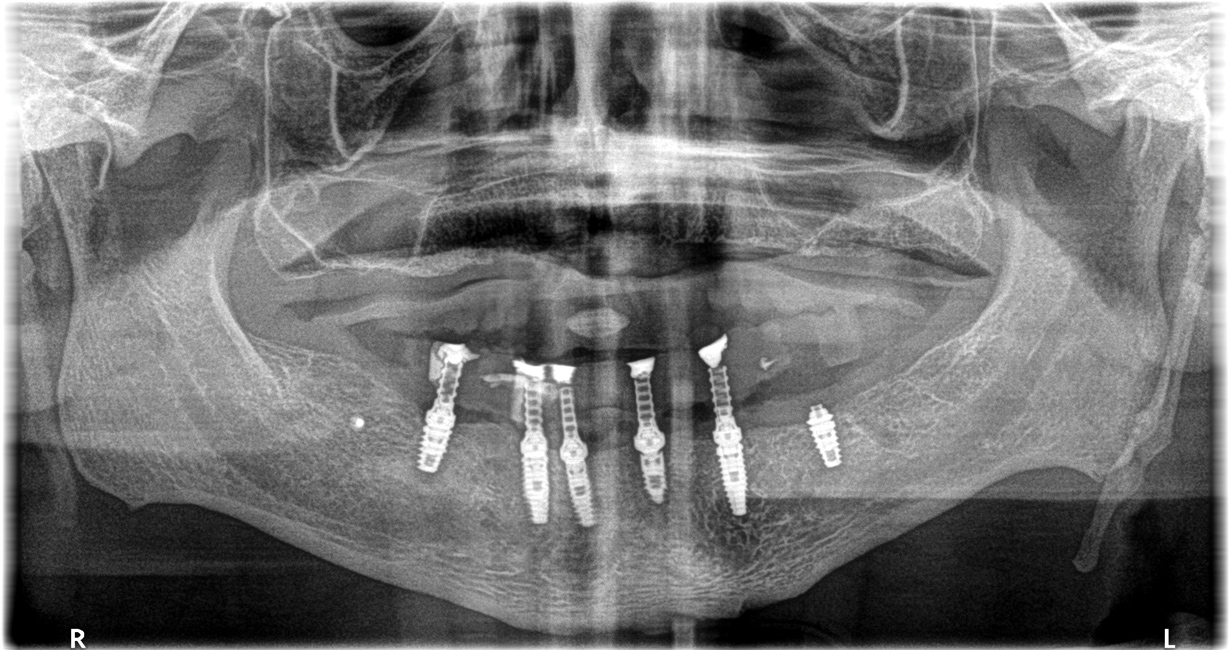

Figure 26: The patient’s final panoramic radiograph shows all surgical placement.

Figure 26